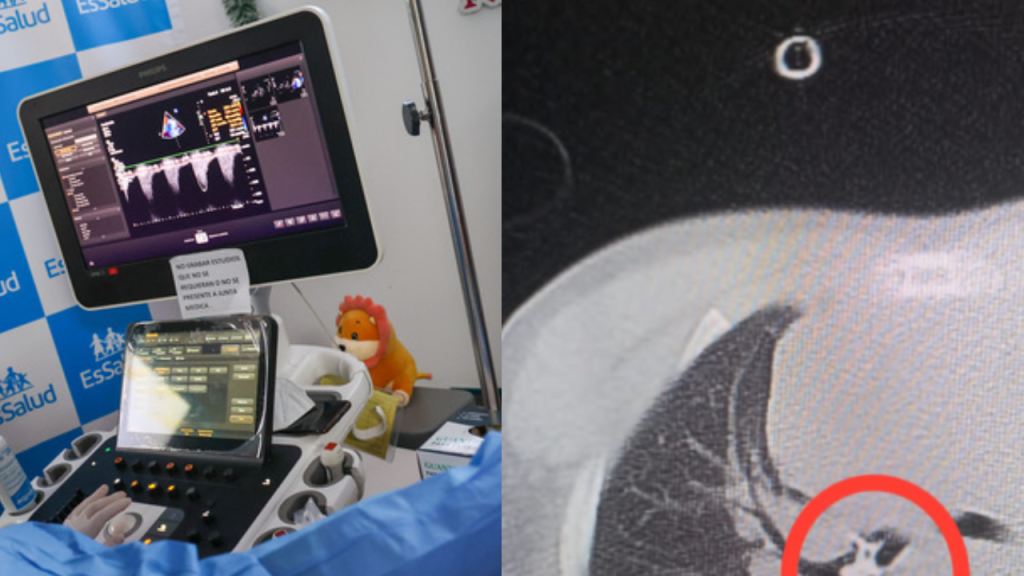

Sin embargo, la situación era más complicado aún y la pieza dental se había alojado en un bronquio. Ante las grandes dificultades que aún presentaba el niño para respirar fue trasladado en una ambulancia aérea al Hospital Nacional Edgardo Rebagliati Martins en Lima.

“El diente se encontraba en uno de los bronquios principales, creemos que durante la extracción de esta pieza dentaria, el diente atravesó cuerdas vocales, llegó a la vía inferior, alojándose en el bronquio principal izquierdo” explicó el doctor Jairo Curioso Yarlequé, neumólogo pediatra del Hospital Rebagliati.

Por diagnóstico riesgoso y complicado, más de una decena de médicos procedieron con una Broncoscopia Rígida. Con ella la que lograron extraer la muela de manera exitosa y así poner al niño fuera de peligro.

Durante la intervención para extraer el molar, los médicos del Rebagliati detectaron una condición clínica cardiaca congénita denominada Coartación de Aorta, por lo que también se procedió con una angioplastia por cateterismo. Esta intervención también fue exitosa como la primera, y fue detectada a tiempo, lo que evitará complicaciones a futuro.